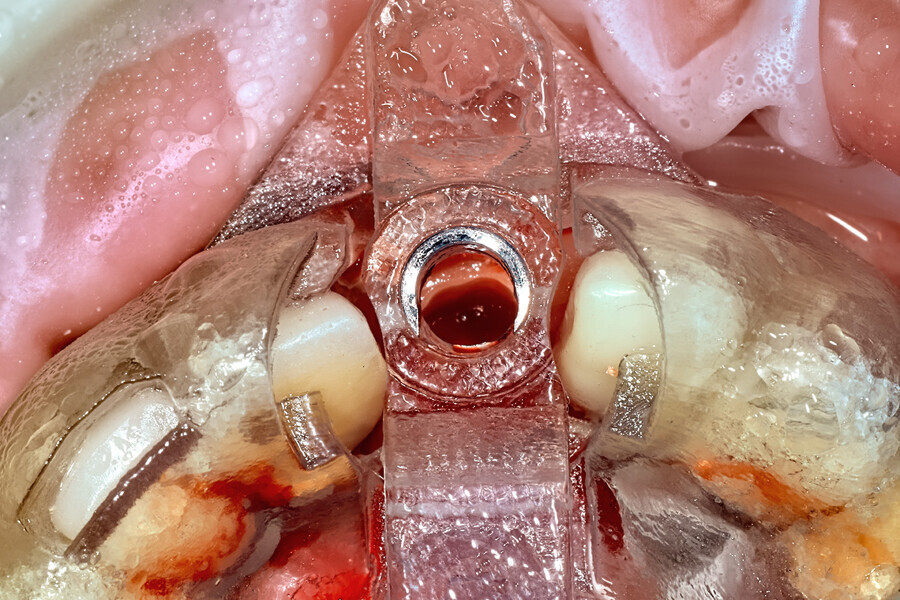

Fig. 23: The implant, seen prior to placement,

using the R2GATE surgical carrier for full-template guidance through the sleeveless guide.